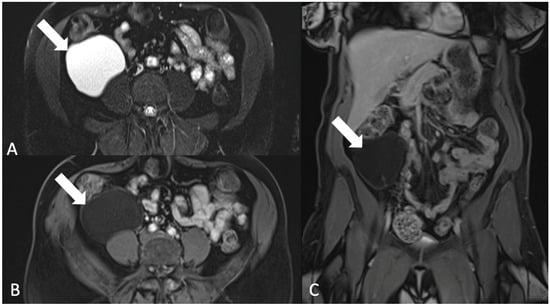

5.4.3. Gastrointestinal Stromal Tumor (GIST)

6. Extraperitoneal Lesions